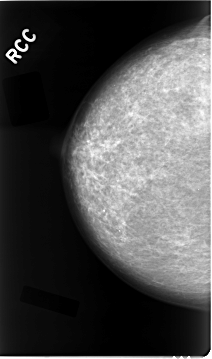

Digital Database for Screening Mammography

Volume: cancer_02 Case: C-0023-1

C_0023_1.RIGHT_CC

RIGHT_CC LINES 4664 PIXELS_PER_LINE 2744 BITS_PER_PIXEL 12 RESOLUTION 50 NON_OVERLAY